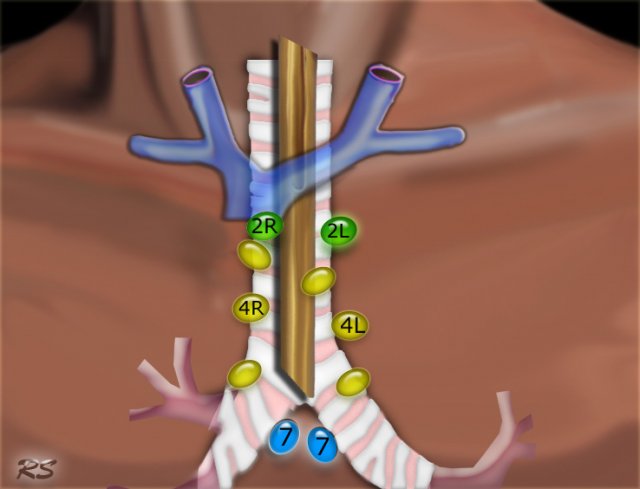

Bản đồ hạch bạch huyết của hiệp hội quốc tế nghiên cứu ung thư phổi – IASLC

Hạch trung thất trên: nhóm 2-4 (Superior Mediastinal Nodes 2-4)

2R. Cạnh trên phải khí quản (Upper Paratracheal)

Hạch cạnh trên phải khí quản đi từ bờ trên cán ức đến vị trí giao nhau của tĩnh mạch vô danh trái với cạnh phải khí quản.

2L. Cạnh trên trái khí quản (Upper Paratracheal)

Đi từ bờ trên cán ức đến bờ trên quai động mạch chủ. Nhóm 2L nằm ở bên trái bờ trái khí quản.

4R. Cạnh dưới phải khí quản (Lower Paratracheal)

Từ chỗ giao nhau của tĩnh mạch vô danh (tĩnh mạch cánh tay đầu trái) với khí quản đến bờ dưới của tĩnh mạch Azygos.

4L. Cạnh dưới trái khí quản (Lower Paratracheal)

Từ bờ trên quai động mạch chủ đến bờ trên động mạch phổi trái.

7. Hạch dưới carina (Subcarinal)

2R. Cạnh trên phải khí quản

Kéo dài từ bờ trên trái của khí quản.

Bờ trên: bờ trên của cán ức.

Bờ dưới: chỗ giao nhau của tĩnh mạch vô danh với khí quản.

2L. Hạch cạnh trái khí quản

Bờ trên: bờ trên cán ức.

Bờ dưới: bờ trên quai động mạch chủ.

4R. Hạch cạnh dưới phải khí quản.

Bờ trên: chỗ giao nhau của tĩnh mạch vô danh với khí quản.

Bờ dưới: bờ dưới của tĩnh mạch Azygos.

4L. Hạch cạnh dưới trái khí quản

Nằm ở bên trái của cạnh trái khí quản, giữa đường ngang được vẽ theo phương tiếp tuyến với bờ trên của cung động mạch chủ với một đường được vẽ theo phương tiếp tuyến với bờ trên của động mạch phổi trái.

Bao gồm các hạch nằm ở giữa dây chằng động mạch.

7. Hạch dưới carina

Nằm ở phía dưới góc carina của khí quản, nhưng không liên quan với thùy dưới hoặc thùy trên của phổi.